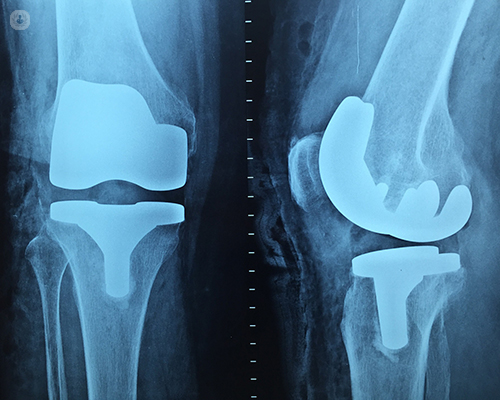

Rotating Platform Knee

The Rotating Platform Knee is based on a revolutionary design technology, the Mobile-bearing Knee. When patients bend their Knees, the surfaces of their joints roll and glide against each other, allowing their knees to rotate as they bend.

Unlike traditional, Fixed-bearing Knee implants, Rotating Platform Knee Implants are designed to mimic this natural movement. This rotation reduces the stress and wear on the implant. Women may be especially interested in this technology, since their Knees rotate more than those of a man during normal movement.

The disadvantage of this Knee is that if there is a gross deformity or imbalance in the ligament, then there are chances of dislocation of the Knee after using rotating platform Knees.